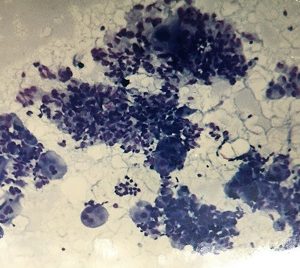

Thyroid Hashimotos Thyroiditis

This video presents a summary of changes seen in Hashimoto’s Thyroiditis